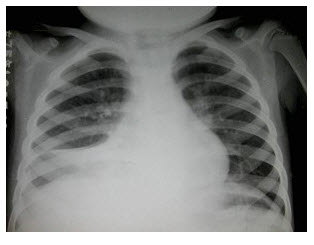

16、单项选择题

男,32岁,2天前被人踢伤胸部,感胸闷、呼吸困难,X线检查如图,最可能的诊断为()

A.左侧气胸

B.左侧胸腔积液

C.左侧胸膜肥厚

D.左侧液气胸

E.左侧肺挫伤